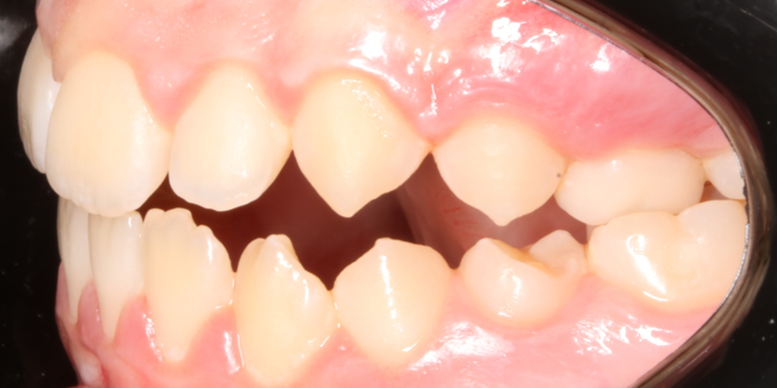

Llama la atención a primera vista la mordida abierta bilateral, especialmente pronunciada entre el cuadrante 1 y 4 debido a una interposición lingual en posición estática. Entre otros hallazgos fundamentales, observamos: un patrón dolicofacial severo (VERT: -2), una compresión de la arcada superior que cursa con un perfil y relación oclusal de clase III y la rotación del 35 y 45. Este caso se trató con un disyuntor, exodoncias de 44 y 34, brackets convencionales y educadores para rehabilitación de la lengua en un tiempo de 22 meses. Aunque estoy satisfecho con el resultado final, me hubiera gustado clavar la interscuspidación de premolares en el cuadrante I y IV, y mejorar la relación oclusal de cuadrante II y III. Sin embargo, lo bonito, es que hay a veces, en la ortodoncia real, que el paciente está satisfecho y quiere terminar antes de tiempo, o por el contrario, que el profesional intenta pero no consigue el resultado deseado. Y a mí más que compartir casos perfectos, me gusta mostrar mis errores, mi realidad.

La ilustración nos deja entrever algo tan fácil como que en un paladar pequeño no entra una lengua grande. Y viceversa, en un paladar grande entra una lengua grande. Llevándonos dicha explicación al caso que nos atañe, podemos ver  en la fotografía lateral del lado derecho como la lengua escapa y busca espacio, de manera permanente, entre el cuadrante 1 y 4,  estímulo que mantenido en el tiempo generó en una mordida abierta lateral.